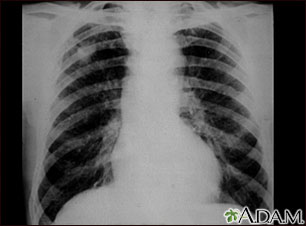

This chest X-ray shows coal workers pneumoconiosis - stage II. There are diffuse, small (2 to 4 mm each), light areas throughout both lungs. In the right upper lung (seen on the left side of the picture), there is a light area (measuring approximately 2 cm by 4 cm) with poorly defined borders, representing coalescence (merging together) of previously distinct light areas. Diseases which may explain these X-ray findings include simple coal workers pneumoconiosis (CWP) - stage II, silico-tuberculosis, disseminated tuberculosis, metastatic lung cancer, and other diffuse infiltrative pulmonary diseases.